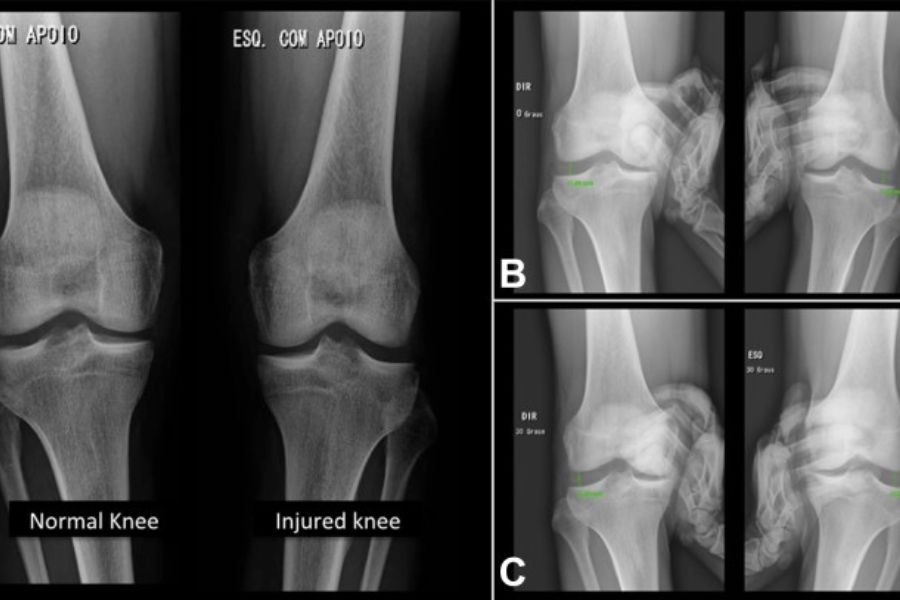

5. Ciddi Durumlarda Gelişmiş Görüntüleme ve Rehabilitasyon

Yumuşak dokularda yırtık şüphesi varsa, MR gibi görüntüleme yöntemleri ile detaylı değerlendirme yapılabilir.